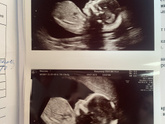

Прошла платно второй скрининг, бесплатный будет на 21,4 недели, даже уже сомневаюсь идти или нет, по узи все отлично ??? Доченька уже 280 грамм весит, плацента поднялась. Сердечко работает отлично.